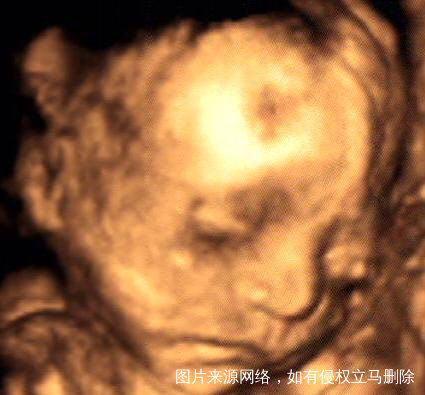

四维通过,大家都来接吧